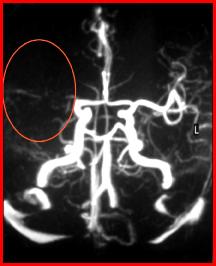

Thrombotic infarctions are frequently due to the occlusion of arteries by atherosclerotic debris and subsequent obstruction by thrombotic material. Usually these lead to nonhemorrhagic infarctions resulting in liquefactive necrosis.

Here are 3 angiograms. Each case represents either a thrombotic, hypoperfusion, and hemorrhagic stroke. Which is which?

What would thrombosis of an artery look like on an angiogram?